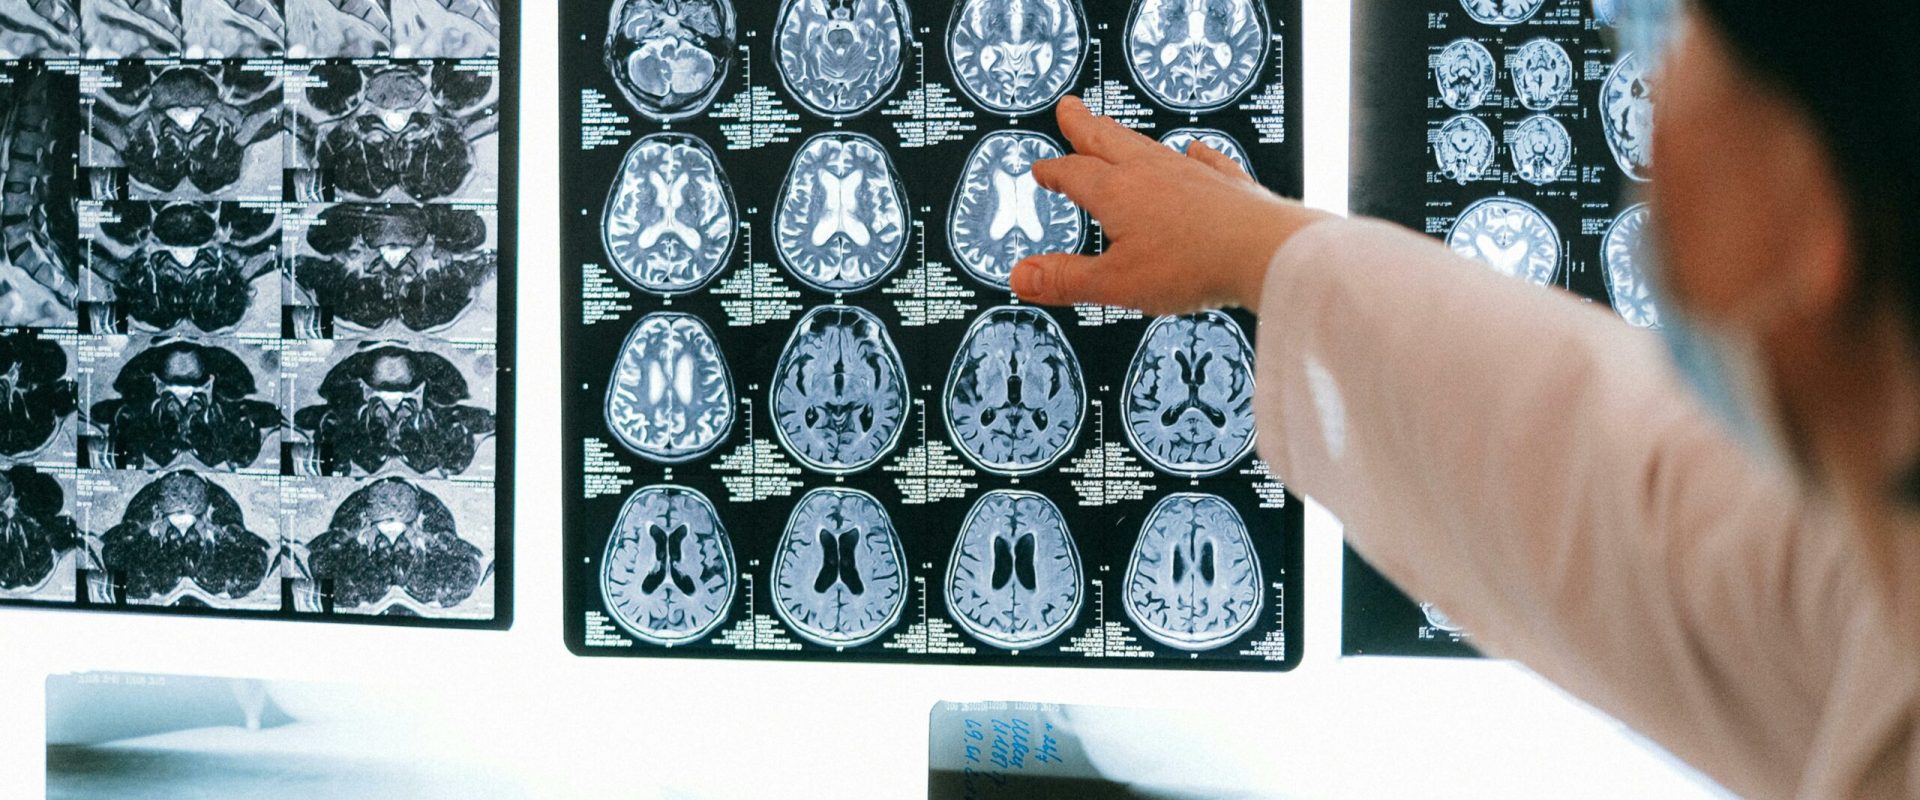

NHS England a introdus o tehnologie de scanare a creierului care reduce semnificativ timpul de diagnosticare a accidentelor vasculare cerebrale, oferindu-le pacienților șanse mai mari de recuperare. Noua metodă permite medicilor să intervină rapid, triplând astfel posibilitatea recuperării fără dizabilități.

Scanarea cerebrală utilizată de NHS a demonstrat eficiență în scurtarea cu peste 60 de minute a timpului de așteptare pentru tratament. Această eficiență este crucială, având în vedere că fiecare minut contează, iar celulele cerebrale mor cu o rată de aproximativ 2 milioane pe minut în timpul unui accident vascular cerebral. Cu cât intervenția medicală este mai rapidă, cu atât rezultatele sunt mai favorabile pentru pacienți.

David Hargroves, director clinic național pentru accident vascular cerebral al NHS Anglia, a subliniat importanța acestei tehnologii de asistență în luarea deciziilor, afirmând că aceasta revoluționează modul în care sunt tratați pacienții cu accidente vasculare cerebrale. Acest software bazat pe inteligență artificială oferă interpretări precise în timp real, ajutând personalul medical să ia decizii rapide.